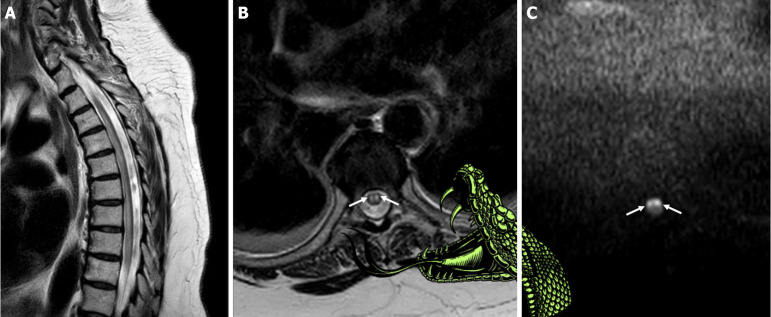

Descriptive signs in radiology can aid in easier pattern recognition and quicker diagnosis. In spinal cord ischemia, paired anterior-horn T2-hyperintensities have traditionally been known as the "owl's eyes" or "snake eyes" sign. We discuss how these signs, while visually apt, convey no pathophysiologic context and propose renaming this finding the "snake bite sign". The image still evokes two punctate marks, yet the metaphor extends to a snake bite (two fang-like dots) rather than two bright foci (eyes) staring back at the viewer. Moreover, besides the sign metaphorically resembling a traumatic puncture of the two fangs, on the occasion of a venomous snake bite occurring elsewhere, additional neurological consequences may occur, paralleling the neurological deficits seen in anterior spinal artery infarction and several mimicking myelopathies, thus further highlighting the analogy. Such clinically driven terminology may facilitate teaching, enable diagnostic recall, and improve interdisciplinary communication.